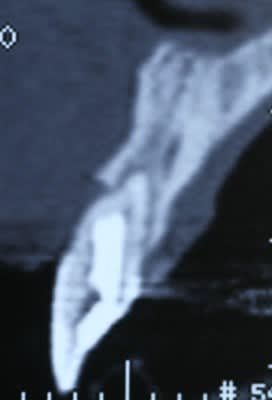

fig 1 coupe tomo Jo

fig 2 vue clinique ( léger décalage des collets entre 11 et 21 )

fig 3 exo

fig 4 pose membrane résorbable + os xénogène

fig 5 membrane suturée

fig 6 réouverture J0 + 6mois

fig 7 vue clinique J0 + 2ans ( Prothèse Dr G.D 31 )

fig 8 vue clinique JO + 5ans (léger décalage des collets entre 11 et 21 comme à l'origine)

fig 9 radio J0 + 5 ans